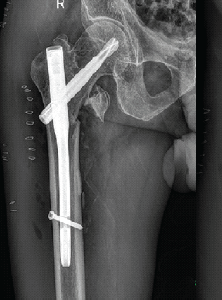

A Rare Case of Pseudoaneurysm of Profunda Femoris Artery Following Surgical Fixation of an Intertrochanteric Fracture

Shrihari L Kulkarni , Manjunath Daragad , Ravikiran R , N Manoj

………………………………p.174-178